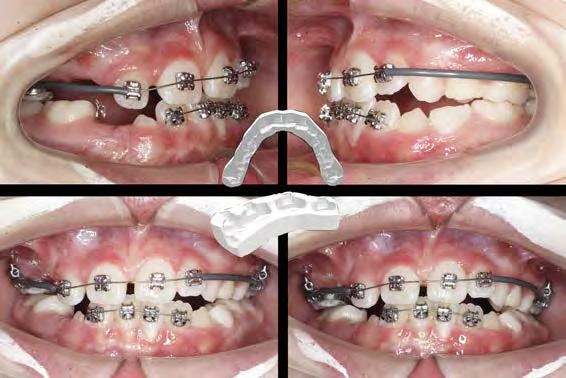

Férula de Descarga Digital de Nylon

La primera Férula de Descarga para tratar a pacientes con bruxismo y problemas de la ATM utilizando la tecnología más avanzada en impresión 3D.

Tecnología CAD/CAM para una óptima precisión y adaptación de la férula

Fabricada en Poliamida 12 con certificado en biocompatibilidad Clase IIa

Ligera, cómoda y con una alta resistencia al desgaste y a las fuerzas de la boca

(+34) 952 212 174info@ortoplus.eswww.ortoplus.es atm.ortoplus.es